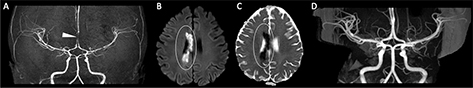

Fig 3

Figure 3. An 11-year-old previously healthy male who presented with left-sided headache, emesis and changing voice. Axial (A) and coronal (B) CT images of the head demonstrate a geographic region of hypoattenuation in the left superior cerebellar hemisphere with loss of grey-white differentiation (circle). C. Axial DWI from MRI the same day demonstrates corresponding reduced diffusion in the left superior cerebellar artery territory (circle). 2D Time-of-Flight MRA of the neck demonstrate irregularity of the right (D) and left (E) vertebral arteries at the junction of the V2 and V3 segments (arrows). Axial CT angiogram (F) confirms irregularity in the vertebral arteries, compatible with bilateral vertebral artery dissection (arrows).

Fig 6

Figure 6. ACTA2 Mutation. Axial ADC (A) demonstrates reduced diffusivity in the periventricular white matter, compatible with acute infarct. 3D Time-of-Flight MRA (B) shows enlargement of the internal carotid arteries (arrowheads) with narrowing of the distal internal carotid arteries (arrow). Follow-up axial T2-weighted image (C) shows evolution of the infarct to cystic encephalomalacia. Case courtesy of Dr. Tamara Feygin, Department of Radiology, Children’s Hospital of Philadelphia.